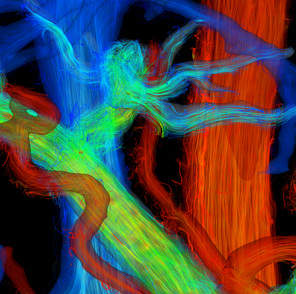

Small Animal Imaging